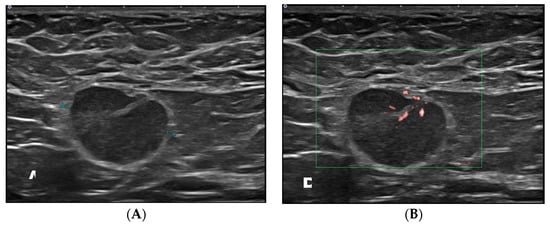

2.2. Ultrasound Technique

- Cocco, G.; Delli Pizzi, A.; Fabiani, S.; Cocco, N.; Boccatonda, A.; Frisone, A.; Scarano, S.; Shiavone, C. Lymphadenopathy after the anti-COVID-19 Vaccine: Multiparametric ultrasound findings. Biology 2021, 10, 652. [Google Scholar] [CrossRef]

- Granata, V.; Fusco, R.; Setola, S.V.; Galdiero, R.; Picone, C.; Izzo, F.; D’Aniello, R.; Miele, V.; Grassi, R.; Grassi, R.; et al. Lymphadenopathy after BNT162b2 Covid-19 vaccine: Preliminary ultrasound findings. Biology 2021, 10, 214. [Google Scholar] [CrossRef]